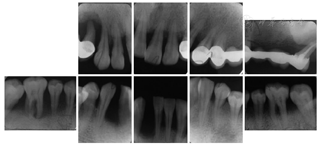

(2)临床检查:口腔卫生状况较差,大量菌斑、软垢,牙石++~+++,可探及大量龈下牙石;牙龈普遍暗红色,龈缘圆钝,质地松软;全口牙邻面探诊深度普遍6~9 mm,出血指数4,双侧上后牙伴探诊溢脓,可及附着丧失;全口牙龈退缩3~5 mm;

根分叉病变(furcation involvement,FI)3度,电活力测58,对照牙56。全口根尖X线片见图1,牙周检查表见图2。全口牙列不齐,上下前牙散在间隙,